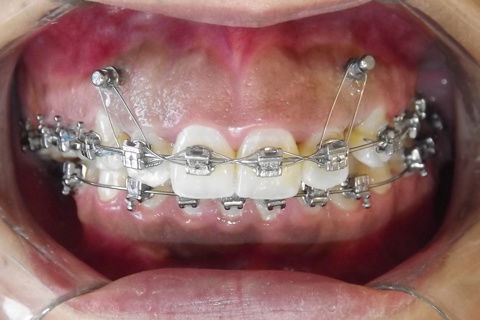

Foto após 22 meses.

Resumo

Paciente do sexo feminino

Primeira opção sugerida foi Cirurgia Ortognática, porém paciente não aprovou.

Foi sugerido uma conduta de distalização superior(alertamos a pacinte quando a mudança do angulo naso-labial) com uso de M.P.O. com poucas chances de sucesso.

O caso esta me impressionando muito pelos resuldados que estão aparecendo.